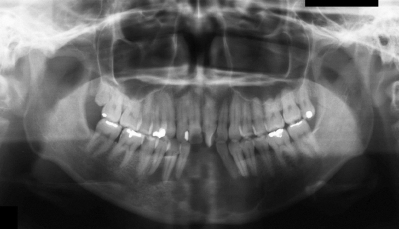

37歳の女性。下顎前歯部の無痛性の腫脹を主訴として来院した。1か月前にかかりつけ歯科医で下顎前歯を抜去されたが、改善しないという。初診時のエックス線写真、CT及び生検時のH-E染色病理組織像を示す。

診断名はどれか。1つ選べ。